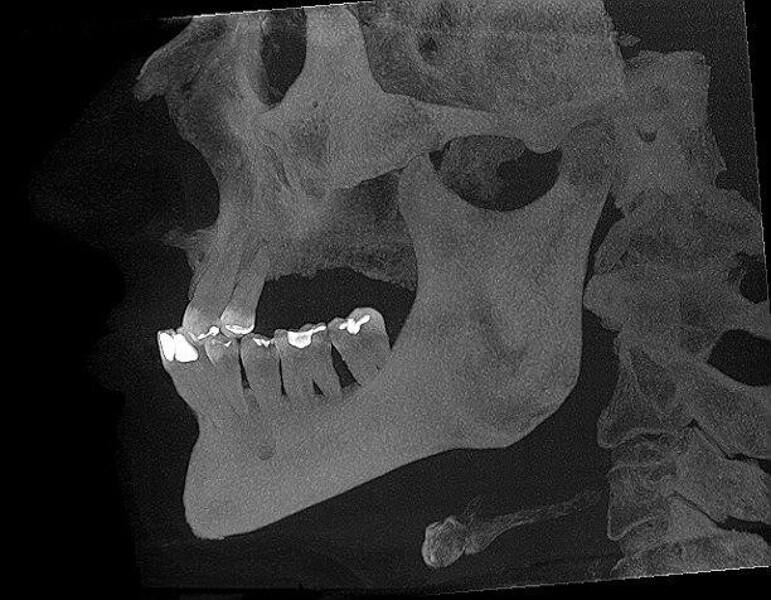

Implantacja z wykorzystaniem szablonu nawigacyjnego 3D